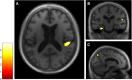

Although deficits in learning and retrieving new information are well characterized in dementia with Lewy bodies, autobiographical memory has never been explored in this disease. Yet, autobiographical memory impairments are a pervasive feature of dementia, well characterized in other neurodegenerative diseases. Moreover, autobiographical memory corresponds to an extension over time of the self, which we hypothesize is altered in dementia with Lewy bodies and impairment of which could be linked to the insular atrophy occurring from an early stage of the disease. In this study, we sought to characterize autobiographical memory impairments and explore their neural correlates in dementia with Lewy bodies, on the assumption that insular damage could impact the self, including its most elaborate components, such as autobiographical memory. Twenty patients with prodromal to mild dementia with Lewy bodies were selected to participate in this exploratory study along with 20 healthy control subjects. The Autobiographical Interview was used to assess autobiographical memory. Performances were compared between patients and control subjects, and an analysis across life periods and recall conditions was performed. 3D magnetic resonance images were acquired for all participants, and correlational analyses were performed in the patient group using voxel-based morphometry. The behavioural results of the Autobiographical Interview showed that autobiographical memory performances were significantly impaired in dementia with Lewy body patients compared to control subjects in a temporally ungraded manner, for both the free recall and the specific probe conditions (P < 0.0001), though with greater improvement after probing in the patient group. Furthermore, autobiographical memory impairments were correlated with grey matter volume within right insular cortex, temporoparietal junction, precuneus, putamen, left temporal cortex, bilateral parahippocampus and cerebellum, using a threshold of P = 0.005 uncorrected. The behavioural results confirm the existence of temporally ungraded autobiographical memory impairments in dementia with Lewy bodies, from the early stage of the disease. As we expected, neuroimaging analysis revealed a role for the insula and the precuneus in autobiographical memory retrieval, two regions associated with elementary aspects of the self, among other brain regions classically associated with autobiographical memory, such as medial temporal lobe and temporoparietal junction. Our findings provide important insights regarding the involvement of the insula in the self and suggest that insular damage could lead to a global collapse of the self, including its more elaborated components, such as autobiographical memory.